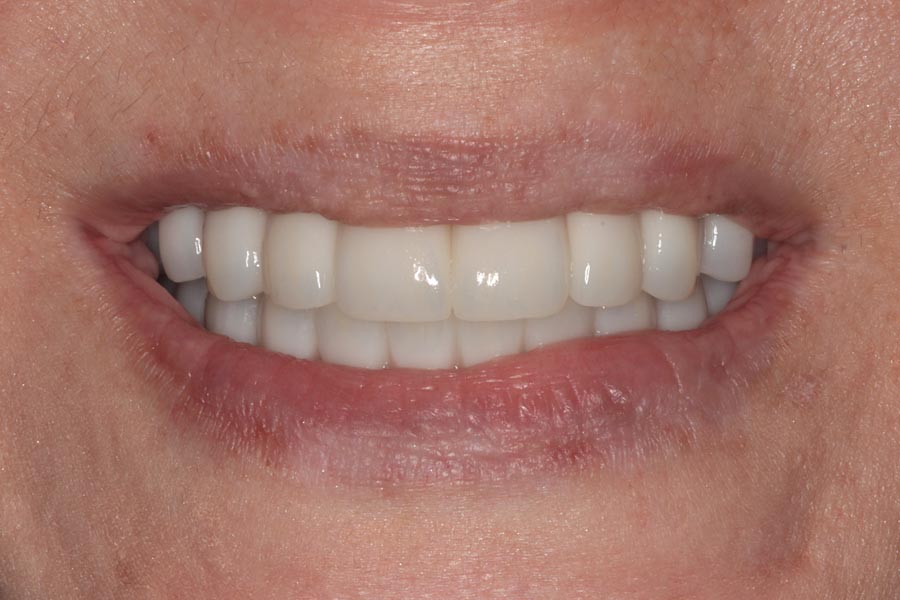

The definitive bridges are delivered, the bite is verified, and the screws are torqued down firmly. The final result is strong, functional, and esthetic restorations that will serve the patient well for years to come.

The patient couldn’t be happier with her new smile. We have improved not only her esthetics but her oral health as well. She now has beautiful restorations she can keep for years to come. Contact us if you would like to have a consultation and see if this is the right treatment for you!